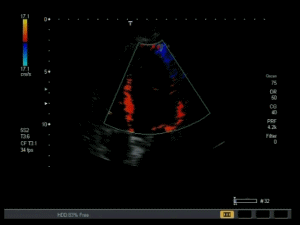

Echokardiographie:

Cardio Hands On

Tissue doppler in der Echokardiographie Kontrastmittel erlaubt erstaunliche Diagnosen